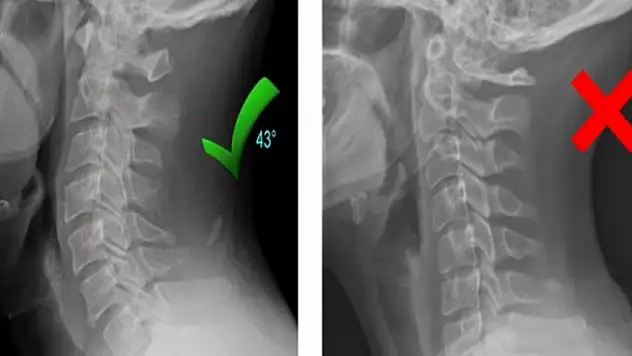

Boyun düzleşmesine karşı uzmanından uyarı